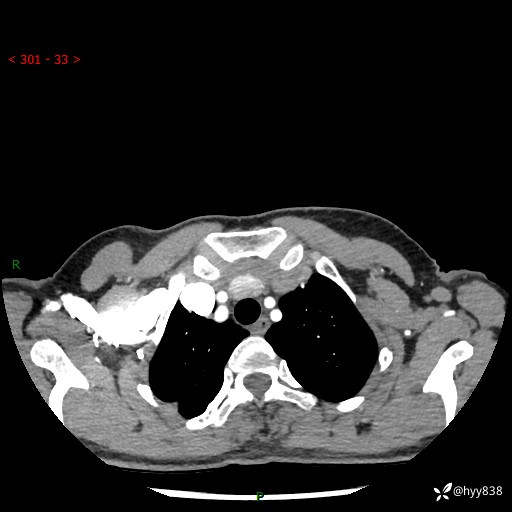

增强动脉期+静脉期